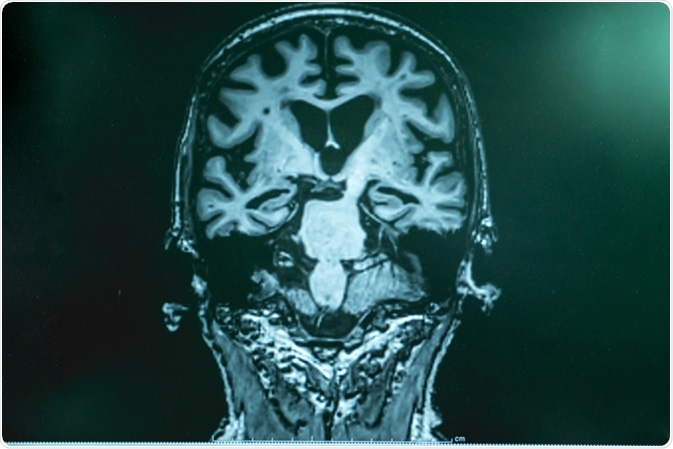

Alzheimer's disease with MRI. Image Credit: Atthapon Raksthaput / Shutterstock

Clinical methods that are also useful in diagnosing dementia include cognitive and neuropsychological tests; laboratory examinations of blood or other body fluids for the detection of hormones, vitamins, and other biochemical parameters; brain scans such as CT, MRI, and PET to detect stroke and other related vascular injuries; psychiatric assessment to detect mental health condition; and genetic tests to detect genetic risk factors related to dementia.